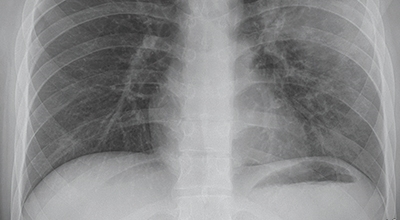

코로나 이후 기관지나 폐가 안좋아진 분 많으시죠. 코로나 이후 3년이 지난 지금도 여전히 코로나에 걸리는 분이 많고 재확진 사례도 주변에서 종종 찾아볼 수 있기에 계속 조심해야 합니다. 오늘은 폐에 좋은 음식 10 가지를 알려드리겠습니다.

건강한 폐를 위해서는 폐의 활동을 유지하는데 도움을 주는 건강에 좋은 음식을 섭취해야 합니다. 폐는 우리 몸에서 중요한 역할을 하는 것은 말할 필요도 없어요. 그러나 결국 폐는 공기 뿐만 아니라 대기 오염과 담배 연기 같은 유해한 요소를 흡입하게 되는데요. 이런 오염 물질은 천식, 기관지염, 낭포성 섬유증 또는 폐렴등의 호흡기 건강 문제의 위험을 증가시켜요.